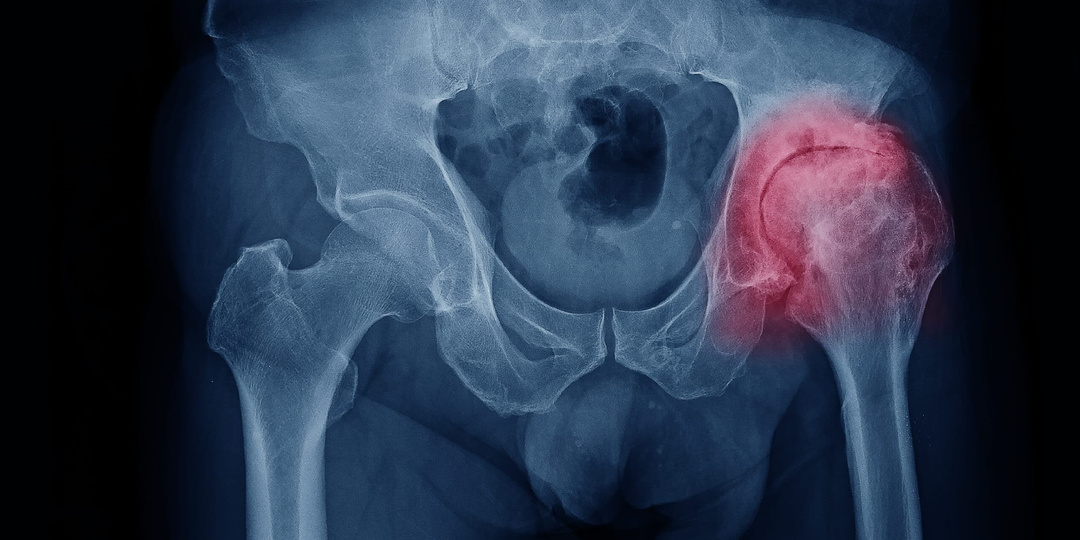

Коксартроз — не повод сдаваться: что реально помогает при боли в тазобедренном суставе?

Когда впервые появляется ноющая боль в бедре, особенно после долгой прогулки или подъёма по лестнице, многие списывают это на усталость или «возраст». Но если дискомфорт не проходит, а со временем усиливается, становится трудно надевать обувь, сидеть за рулем или просто подниматься с дивана — пора задуматься: а не коксартроз ли это? Это слово звучит пугающе. Оно ассоциируется с хрустом, хромотой, операциями, потерей подвижности. Многие считают, что коксартроз — это приговор: раз начался, значит, неизбежно приведёт к инвалидности. Но так ли это на самом деле? Можно ли остановить его? Вернуть себе лёгкость движений? И главное — можно ли вылечить коксартроз? Давайте разберёмся без паники и без ложных обещаний — просто по фактам, понятно и честно. Что такое коксартроз — на пальцах Коксартроз — это дегенеративное заболевание тазобедренного сустава. Проще говоря, постепенное «изнашивание» хряща, который покрывает головку бедренной кости и суставную впадину таза. Этот хрящ — как амортизатор